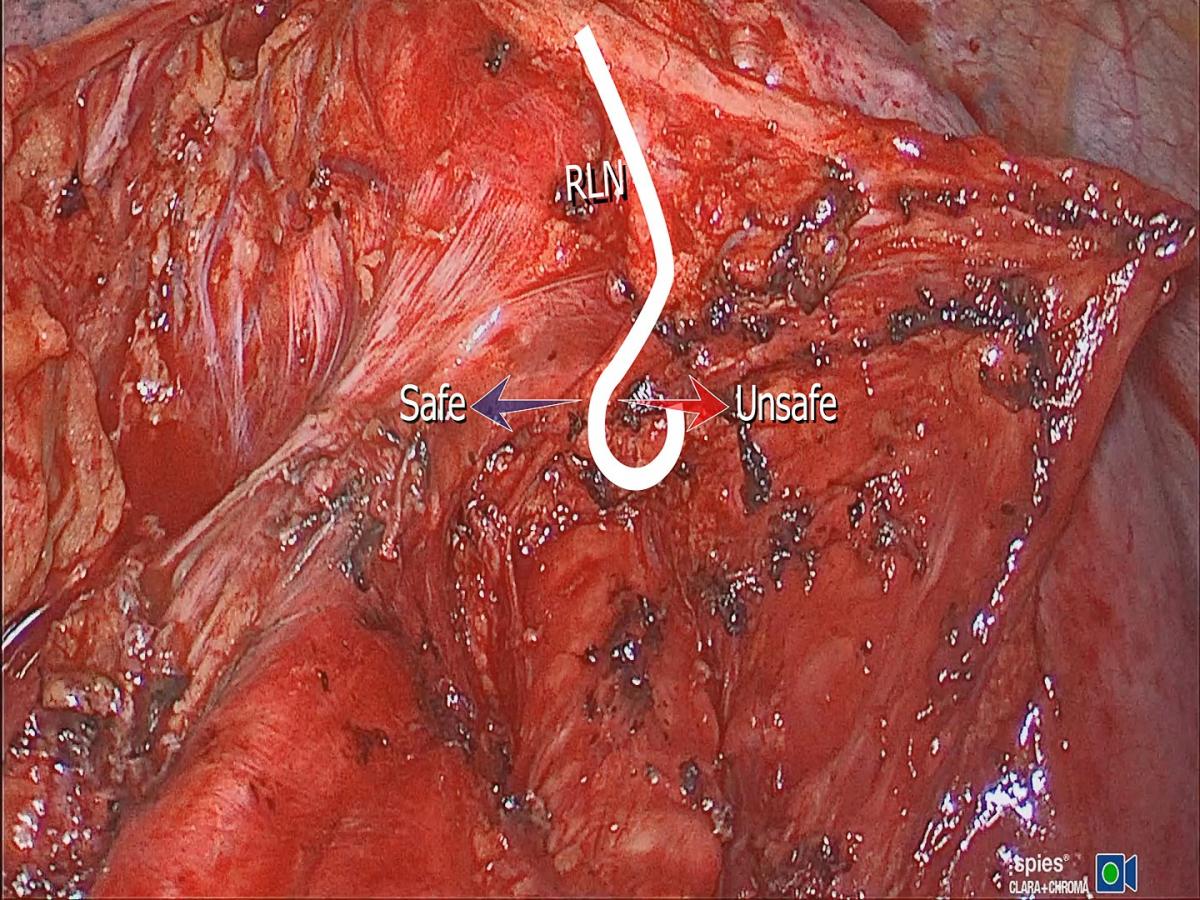

Figure 3. Freshly embalmed human cadaver. The aorta was transected at the origin of the ligamentum arteriosum to expose the motor branch in RLN zone 3.

In its second zone, the RLN usually splits from the vagus but runs very close and medial to it. Therefore, the thoracic surgeon might see one or two nerves side-by-side over the aortic arch. The caliber of the RLN is about 1 mm, or half that of the vagus nerve, but sizable enough to distinguish it from the sensory twigs that arise from it. At the point of origin of the ligamentum, the vagus nerve continues to descend over the back of the hilum, anterior to the descending aorta to reach a course lateral to the esophagus below the inferior pulmonary ligament. It is at this point of reflection at the ligamentum that the vagus nerve (as well as the RLN) gives sensory and autonomic nerve twigs to the surrounding structures (main trachea, esophagus, left main bronchus, cardiac branches, main pulmonary artery and nodal pack). This is a replica of the organized chaos seen on the right side. These twigs work like ropes that fix the vagus nerve and the RLN to the point of reflection around the ligamentum. They weave up a mesh that traps lymph nodes like trapped fish in a fisherman’s net (station 5 and 4L). The main motor branch is what the thoracic surgeon should be concerned about. The latter continues under the aortic arch into zone 3, retaining the same caliber seen over the arch, in contradistinction to the sensory twigs, which are considerably smaller in size. Similar to the right side arrangement, it is these sensory fibers that cause confusion of identification and fear of iatrogenic injury. Previously it was thought that disconnection of these sensory twigs is related to vocal chord palsy, which is not the case. The course of the motor part of the nerve as it disappears under the ligamentum has baffled surgeons for a long time. Very little is seen of the motor branch before it disappears under the aortic arch. The course of the nerve from the ligamentum to the point where the nerve reaches the tracheoesophageal groove is only few millimeters, but seems to be completely baffling to the thoracic surgeon. Contrary to common belief, the motor nerve does not ascend to the left hand side but to the right side to reach the groove (viewed from a thoracotomy incision or VATS lateral view). Figure 3 shows a cadaveric photograph taken from a freshly embalmed body, courtesy of Professor Rajinder Parshad, The All India Institute of Medical Sciences. It shows a transected aorta at the point of origin of the ligamentum arteriosum. The vagus nerve was slung using a suture material. The course of the motor RLN is shown clearly, and the difference in caliber compared to the sensory twigs is worth noting. Dissection for station 4L and 5L could be facilitated by deliberate cutting of these sensory twigs. Care should be taken to disconnect them using a bipolar device, close to their target destination, to minimize spread of energy to the motor branch. It is perfectly safe to do so, with no consequences or voice complications. The trick is to identify the motor branch and keep an eye on it at all times. Although not necessary, stapling and cutting the ligamentum arteriosum improves exposure of zone 3 of the nerve and facilitates nodal harvesting of station 4L, as well as making it possible to sample 4R precarinal (N3 nodes) anterior to the main trachea. Blind diathermy under the arch, or blind fishing for nodes with a ring forceps, even after identifying the recurring motor branch might disconnect the motor branch on its way to the trachea-esophageal groove. It is safe to dissect tissues and fibers to the left of the motor branch, but unsafe to do the same on the right side of the motor branch (Figure 4). There is a constant sensory twig to the left of the reflection point that supplies the pulmonary artery, which is a major cause for confusion and procrastination in decision taking. No nerve should be disconnected until the surgeon has decided beyond doubt that it is not the motor branch.